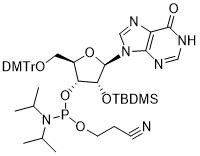

馬鞍山致研生物醫(yī)藥科技有限公司成立于馬鞍山市鄭浦港新區(qū)現(xiàn)代產(chǎn)業(yè)園。公司專(zhuān)注于生物小分子、醫(yī)藥中間體相關(guān)產(chǎn)品的研發(fā)和生產(chǎn),產(chǎn)品主要包括DNA亞磷酰胺單體、RNA亞磷酰胺單體、特殊單體以及按照客戶(hù)要求定制的RNA和DNA,并且公司提供定制合成等方面的研究服...

馬鞍山致研生物醫(yī)藥科技有限公司成立于馬鞍山市鄭浦港新區(qū)現(xiàn)代產(chǎn)業(yè)園。公司專(zhuān)注于生物小分子、醫(yī)藥中間體相關(guān)產(chǎn)品的研發(fā)和生產(chǎn),產(chǎn)品主要包括DNA亞磷酰胺單體、RNA亞磷酰胺單體、特殊單體以及按照客戶(hù)要求定制的RNA和DNA,并且公司提供定制合成等方面的研究服...